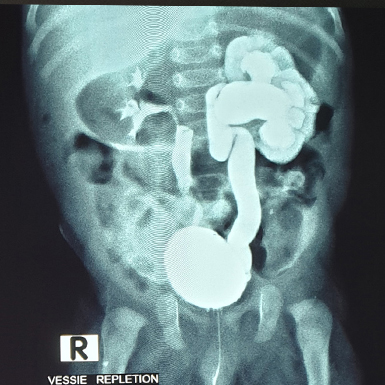

هل يجب إجراء تصوير (Échographie) من أجل التشخيص؟

ليس من الضروري إجراء تصوير طبي لتشخيص التهاب الحويضة والكلية الحاد (Pyélonéphrite aiguë)، إلا أن التصوير قد يكون مفيدًا في بعض الحالات الصعبة أو الغامضة.

أما المناطق منخفضة الصدى (Hypoéchogènes) فهي أقل شيوعًا، وقد تدل على احتمال تكون قيح (Abcès) في الكلية.

وفي بعض الحالات المضللة، قد تُظهر الموجات فوق الصوتية لالتهاب الحويضة والكلية الحاد ما يشبه وجود كتلة داخل الكلية (Masse intrarénale)، مما يستدعي تفسير النتائج بحذر وربطها مع الأعراض السريرية والفحوصات المخبرية.

تعدّ الموجات فوق الصوتية للكلية (Échographie rénale) مفيدة بشكل خاص لاكتشاف أي تشوّه خلقي في المسالك البولية، إذ إن وجود مثل هذه التشوهات يزيد من خطر الإصابة بعدوى المسالك البولية.

ويُفضَّل أن تبدأ فحوصات الكشف عن التشوهات الكلوية بالموجات فوق الصوتية، بعد فترة من انتهاء نوبة العدوى، لضمان دقة النتائج وتجنّب تأثير الالتهاب الحالي على الصورة التشخيصية.